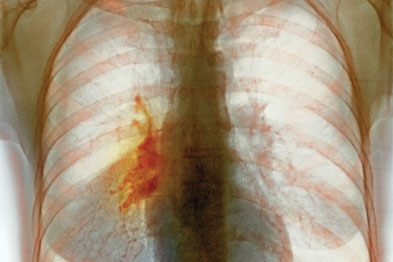

Small Cell Lung Cancer Review Article

Small Cell Lung Cancer Review Article Images